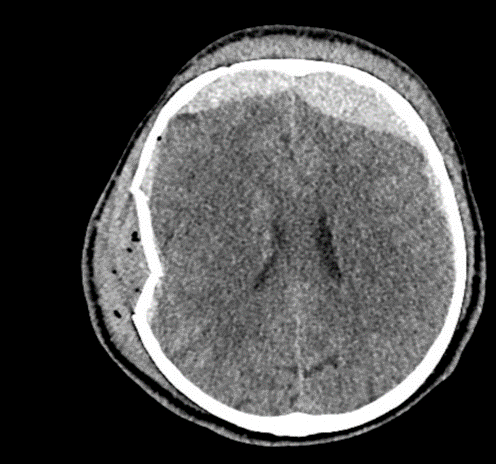

CASE 2 -A 54-year-old man walks into emergency 3 hours after a 150kg plank of wood fell on his head. He has obvious external signs of head injury and a cracking headache, however, neurologically he is intact. A CT head scan is performed

EXPLANATION –There is a depressed right parietal bone fracture with underlying pneumocephalus (indicates an open skull fracture) and a small subdural hematoma.

- Overlying this there is a scalp hematoma.

- There is also a non-displaced fracture in the frontal bone. This fracture crosses the midline and probably has injured the anterior aspect of the superior sagittal sinus.

- Tears of the dural venous sinuses may cause an extradural hematoma (EDH), as in this case. The hematoma is seen external to the compressed superior sagittal sinus.

Extradural bleeds (EDH) are located between the outer layer of dura and endosteal layer of skull. Like in this case, they are usually associated with calvarial fractures.

- They typically demonstrate biconvex or lentiform shape and are limited by sutures as periosteum is attached at the sutures limiting spread of the bleed.

- The source of bleed is arterial in origin, from a middle meningeal artery as opposed to venous in subdural bleeds.

- Up to 10% of EDH are due to venous bleeding, follow the laceration of a dural venous sinus, as we see in this case.

- There is often displacement of the sinus away from the underlying bone. There are three locations characteristic of venous EDH; the vertex, anterior middle cranial fossa and the occipital posterior fossa.

- Hypodense areas within a bleed likely represent unclotted blood suggesting active bleeding.

- As these bleeds are venous, there is not the same urgency for decompression in theatre. In fact, this patient was managed conservatively as operative intervention poses a risk of further damage to the venous sinuses.